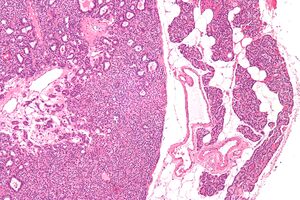

صورة مجهرية لغدوم الجار درقية (يسار) وغدة جارات درقية طبيعية (يمين). صبغة الهيماتوكسيلين واليوزين.